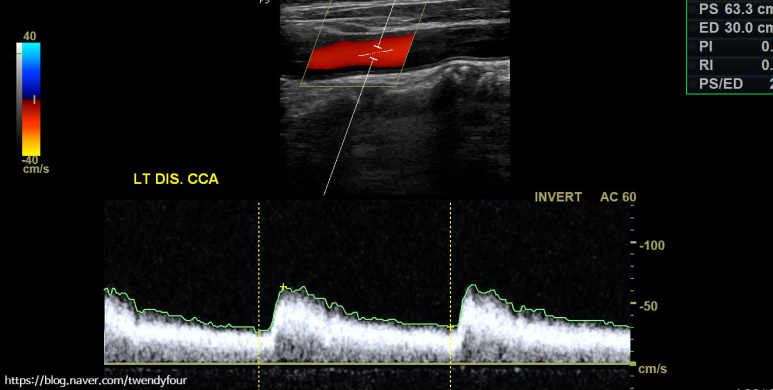

혈류 상태를 컬러로도 확인할 수 있으며, 경동맥 초음파를 정밀 도플러 검사로 혈류 속도를 측정합니다.이 검사를 통해 혈관 벽의 좁기 유무를 확인할 수 있어요.

경동맥의 혈액 순환 속도를 측정해 줍니다.

머리로의 좌측 내경동맥의 혈류속도를 확인하여 협착여부를 간접적으로 확인합니다.눈으로 얼마나 좁아졌는지도 중요하지만 사실 이 검사가 정말 중요합니다.